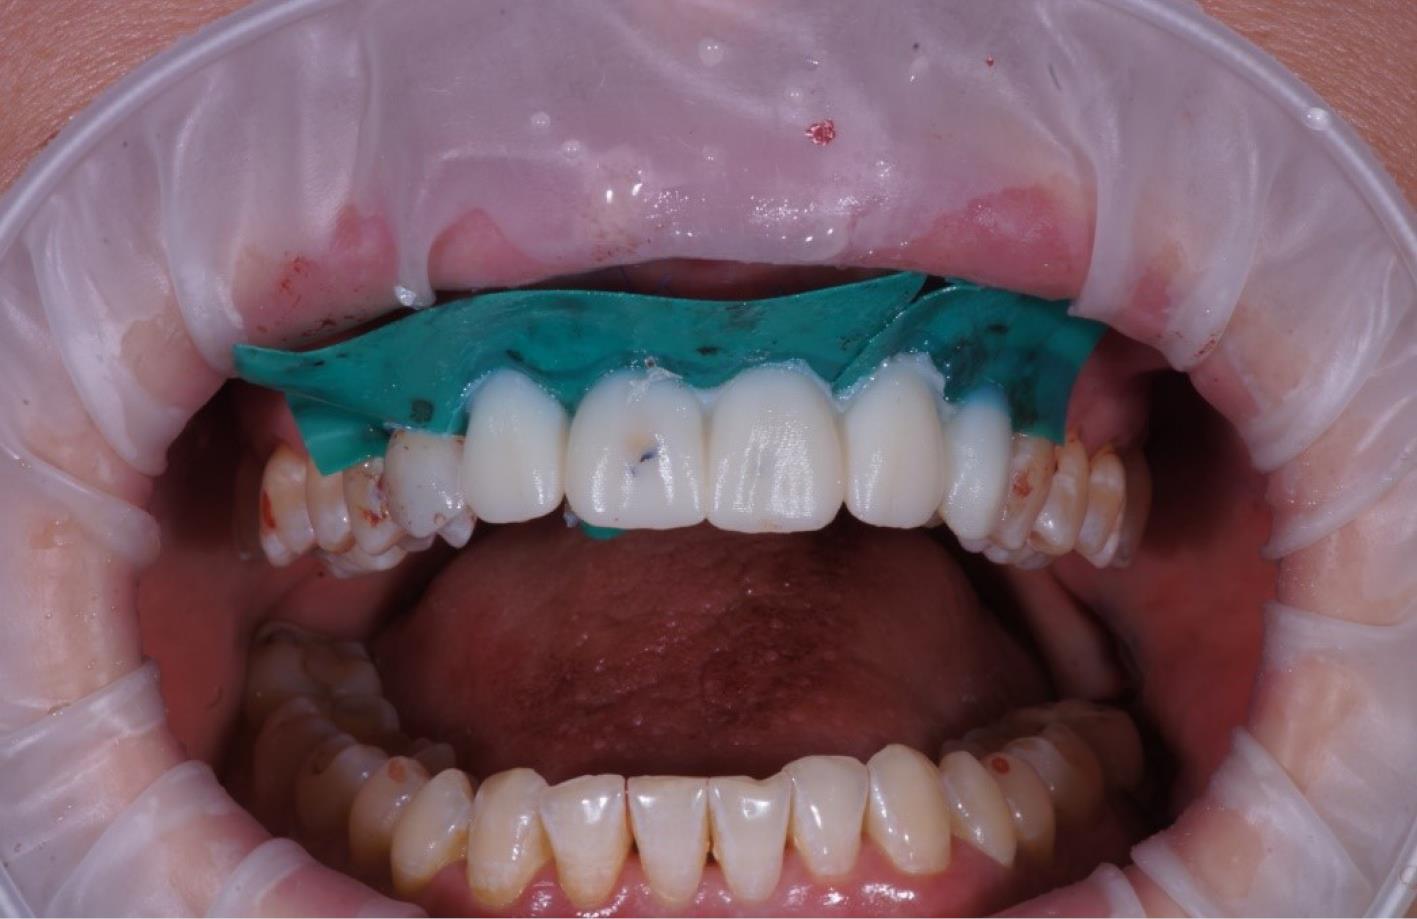

Orthopedic protocol (provisional phase)

The provisional crowns were placed immediately after the completion of the entire surgical phase (Figures 5 and 6). A temporary abutment and bis-acrylic material for provisional restorations in combination with a light-curing composite filling material were used for their fabrication. The sterile titanium provisional abutment was isolated with a collagen sponge to retain the blood clot. The alveolus was isolated with a rubber dam to apply the filling material and prevent infection. The structure was completed outside the oral cavity - modernizing the shape of the sub- and supragingival parts of the orthopedic structure to create a proper fit along the upper contour of the socket and create a space for a blood clot to protect the bone structure. All provisional orthopedic prostheses loaded immediately after implantation had a transocclusive fixation method.

Figure 5.

Soft tissue and gingiva former placement

Figure 6.

Soft tissue graft